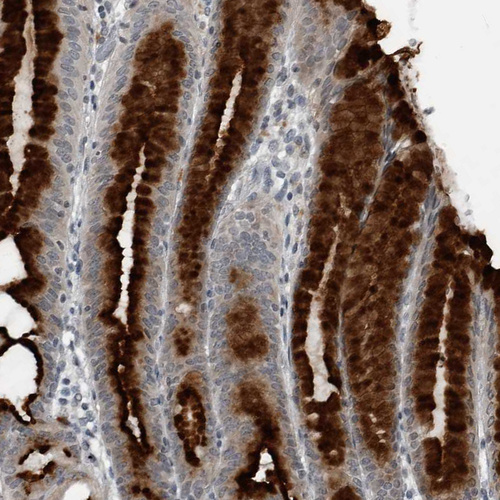

Immunohistochemical staining of human Stomach shows strong granular cytoplasmic positivity in glandular cells.